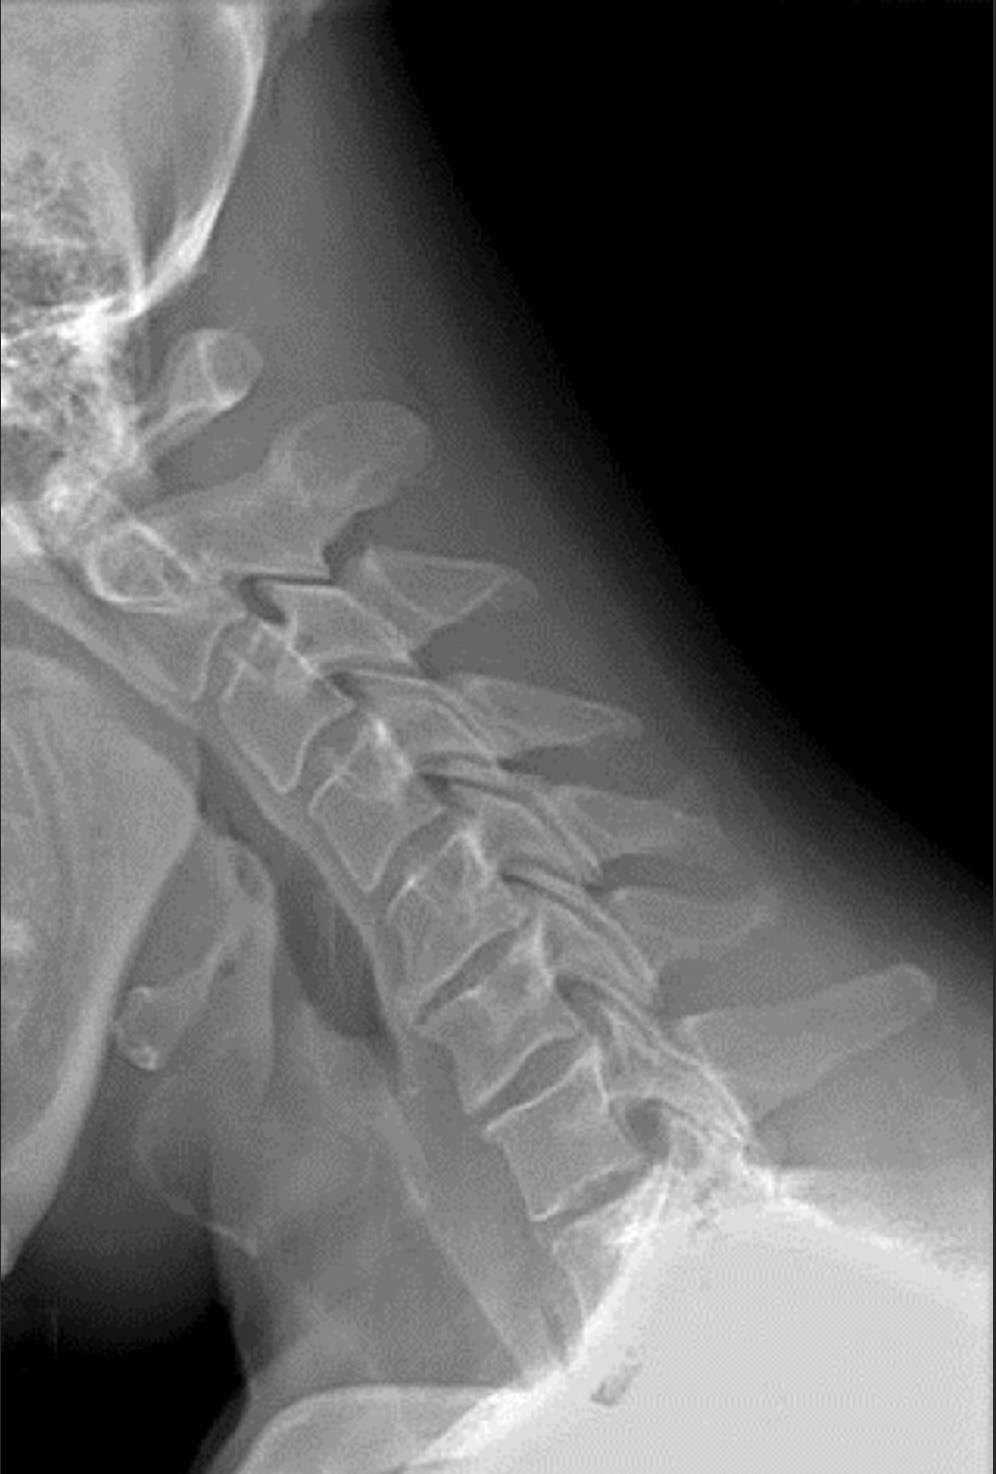

运动损伤之颈椎关节炎

颈椎关节炎是指颈椎椎体和椎间盘(位于骨头之间的圆盘,起到“避震器”作用)的退行性病变。这种退行性病变可能对颈椎产生数种影响,包括骨刺、椎间关节破裂或融合(连接一节脊柱的关节与下一节脊柱相连)、骨孔缩小(骨头上的小孔,神经从中通过)、神经根受压和颈椎管狭窄症。颈椎关节炎的典型症状包括界限模糊的或泛泛的.....

运动损伤之颈椎骨折

发生颈椎骨折的运动员通常出现各种症状,具体取决于骨折的类型及其严重程度。可能出现的症状包括颈部疼痛;脖子活动时出现疼痛;无法活动脖子;上肢麻木、刺痛或无力;或者无法移动四肢。由于颈部骨折的复杂性和潜在严重性,颈部出现疼痛的任何运动员,尤其是有过外伤史的运动员,应该由专业的医务人员进行伤情评估。.....

运动损伤之椎间盘损伤

当颈椎间盘破裂或突出,导致膨胀的组织挤压或刺激颈神经根时,不管是直接的机械刺激还是化学刺激(破裂的颈椎间盘释放各种化学物质,会刺激局部神经和肌肉),就会发生颈椎间盘损伤。颈椎间盘损伤可以单纯地由椎间盘破裂、椎间盘空间变窄、颈椎的神经骨孔变窄、颈椎生成骨赘(骨刺)所导致,也可以由这些病症的任意组合所导.....